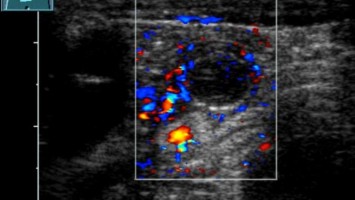

Kind mit "Bauchweh": Liegt die Ursache eine Etage tiefer?

In der pädiatrischen Notaufnahme sind „Bauchschmerzen“ mit der häufigste Vorstellungsgrund. Dabei liegt die Ursache nicht selten eine Etage tiefer.